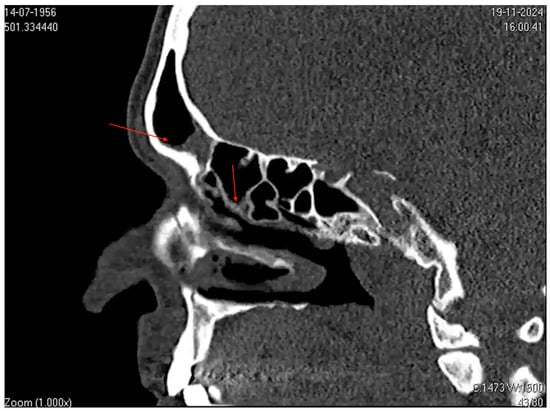

Additionally, CT scans of the paranasal sinuses showed mucosal thickening associated with secretions in the frontal sinuses and ethmoidal cells bilaterally, along with mild mucosal thickening in the maxillary sinuses, consistent with sinusitis (Figure 3). This presentation strongly suggests an underlying infection or an inflammatory process.

Figure 3. Computed tomography (CT) image of the paranasal sinuses in the sagittal plane. The image shows mucosal thickening and partial opacification in the frontal sinus (highlighted by the superior red arrow) and ethmoid air cells (highlighted by the inferior red arrow). Narrowing of the sinus drainage pathways is also evident. These findings are consistent with those of acute and subacute sinusitis.